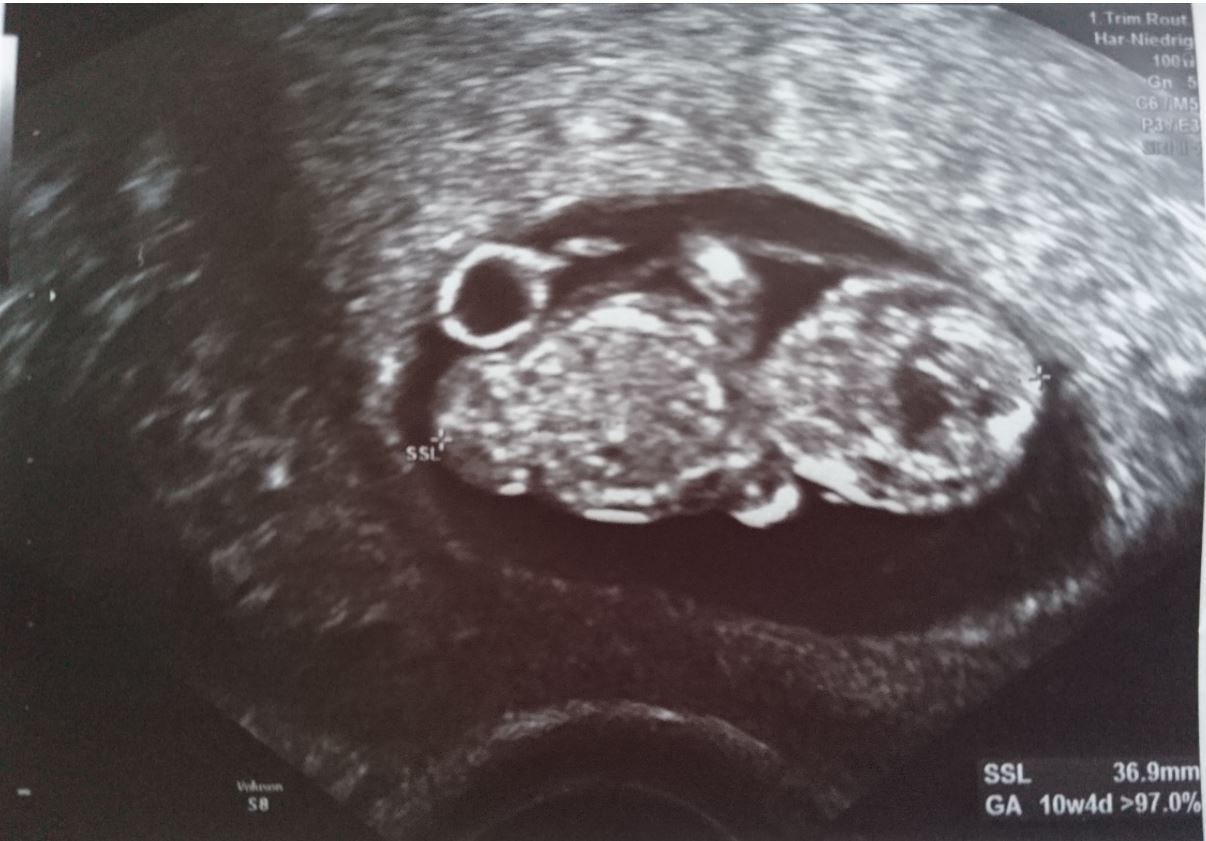

The first picture is taken in 6 wk, the secon 9 wk - both transvaginal.

Attachment 41073Attachment 41074Attachment 41072